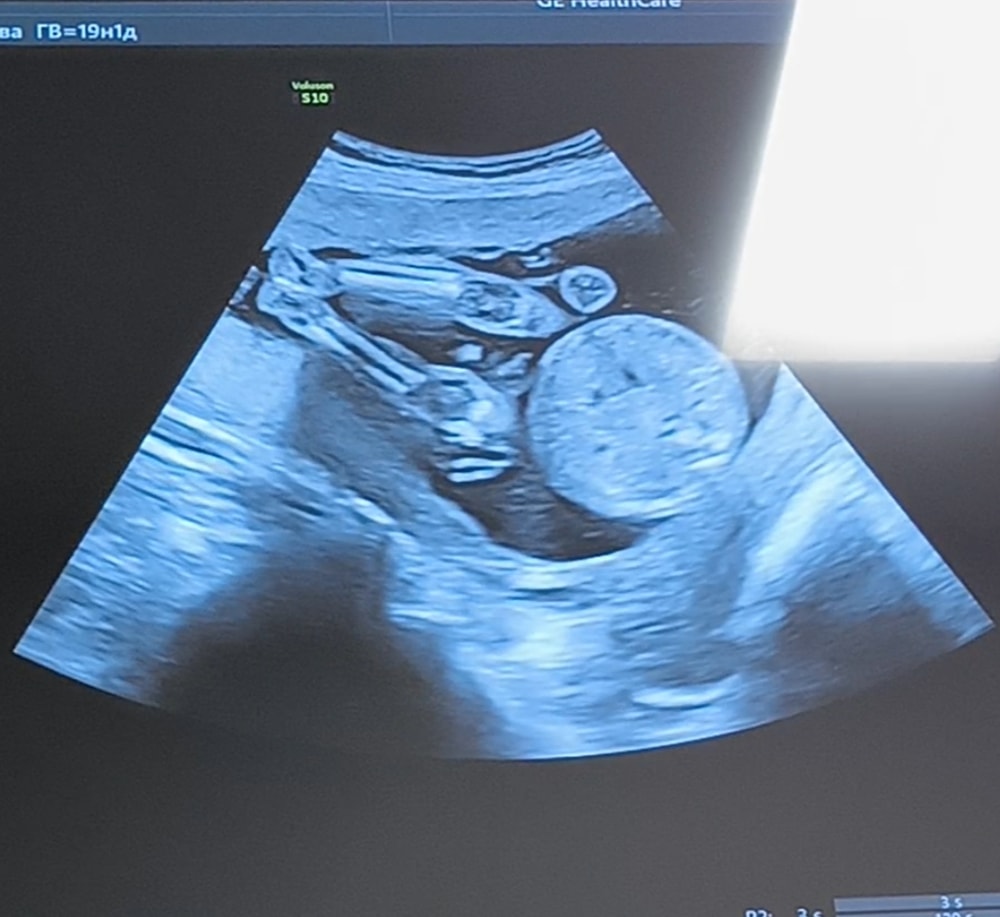

Анализы, скринингиНу что же , 25.11 на сроке 19.3 прошла второй скрининг) Врач сказала что все у нас хорошо, все соответствует норме, слава богу🙏 29 ноября устроим семейный гендер пати, в коробочке будут пинеточки с бантиком нужного цвета, и карточка у вас будет мальчик или девочка 🩷 открывать коробочку будет моя доченька, ей почти 1 годик и 5 месяцев) ещё когда в первом триместре у меня был жуткий токсикоз, я думала что будет девочка, после токсикоза хз, но смотря на видео с УЗИ думаю все таки вторая доченька у нас)

Я так и не стала разбираться в видео на УЗИ 😁только понимаю крупные четкие моменты, типо рука, нога, голова, сердечко бьётся косточки) а вот пол увидеть даже в постах у других девочек ничего не понимаю)